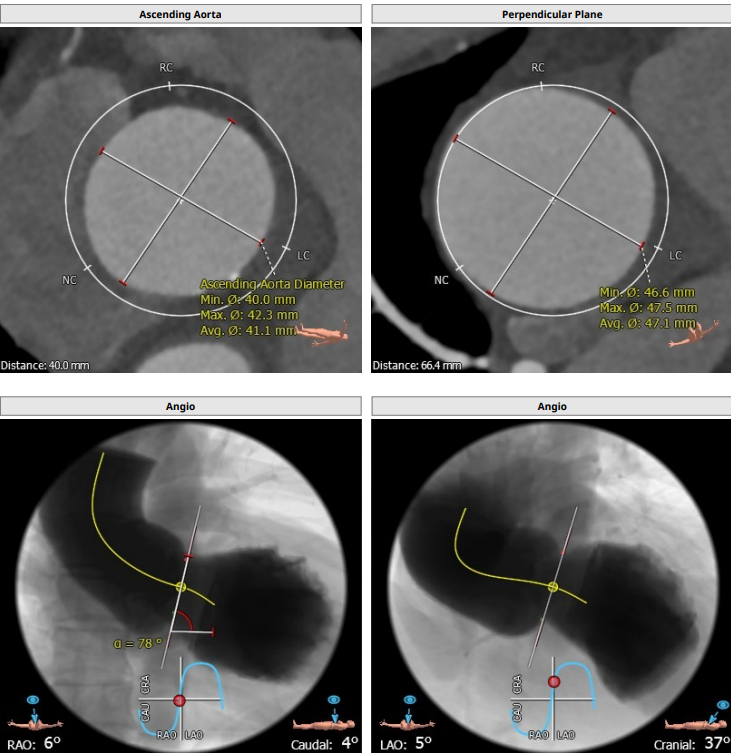

本例患者只有61岁,超声诊断低流速低压差AS,合并升主动脉扩张,CT下测量升主动脉超过50,原则上首选外科手术。但广东省人民医院大血管组会诊后考虑患者低流速低压差,行主动脉瓣和升主动脉置换术,手术风险极高,建议TAVR。从解剖上,瓣环流出道的大小分别是30、31,但瓣上结构是TYPE 0二叶瓣,重度钙化,联合部有钙化融合,瓣上短轴31,窦高度超过23,横位心,角度78°二叶瓣方向呈1点到7点方向。这种解剖做TAVR无疑挑战极大。对于低流速低压差的患者合并解剖挑战的病人,术前计划就是ecmo辅助下TAVR。考虑二叶瓣和重度钙化,目标瓣膜是29号,故用23号球囊预扩,尽量不破坏瓣上结构,另外考虑横位心,升主宽,破裂风险高,瓣膜跨瓣困难,故准备抓捕器辅助跨瓣。投照角度方面准备了瓣膜切线位(左肩),用来跨瓣和球扩,同时准备多一个右足位,这个角度下瓣环和人工瓣膜可以达到共平面,方便瓣膜定位。因为升主宽,横位心,主动脉迂曲,为减少破裂风险,没有选择plus。术中跨瓣遇到较大挑战,因为主动脉根部的角度大,普通的AL2,JR2,多功能导管均无法跨瓣,尝试直头导丝和弯头泥鳅也失败,最后是JL4加直头导丝成功跨瓣。预扩后瓣膜跨瓣尽管在抓捕器辅助下仍然非常困难,在反复尝试后侥幸跨瓣。瓣膜释放后位置偏深,但结合瓣膜角度,瓣周漏可以接受,压差消失,故未再行瓣中瓣。术中未发生停跳,故手术结束后撤去ECMO返回CCU。术后一个月随访EF值明显改善,患者自我感觉明显好转,虽然有中度瓣周漏,但是患者年轻,调整好心功能后,为以后外科置换升主动脉和主动脉瓣打下基础。

患者为type0二叶瓣,重度钙化,78度大横位心,左心明显扩大,EF值为21%,瓣环径为30.1,LVOT31.5,二叶瓣鱼嘴开口初短径为31,钙化融合至对侧为27.5,左右冠高度均为25.7,升主明显扩张。